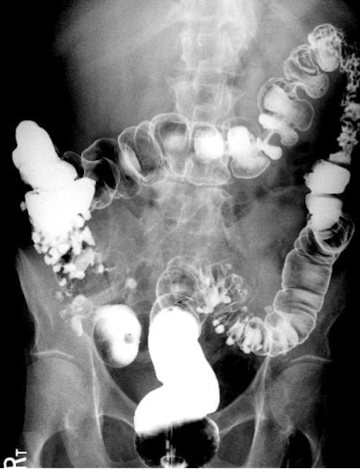

What is this and what type of scan

colon polyp, barium enema